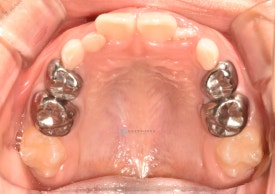

투명교정 10개월차입니다.

치료 후 - 유치 어금니들이 빠지고 영구치가 맹출하고 있습니다.송곳니가 나올 공간을 충분히 마련하며 확장하여 고른치열을 완성했습니다.